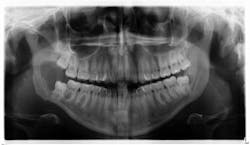

The patient is referred to the oral surgeon for immediate surgery with enucleation. A specimen is sent to the lab for pathology, and a liquid diet is recommended for six to eight weeks (figure 3).